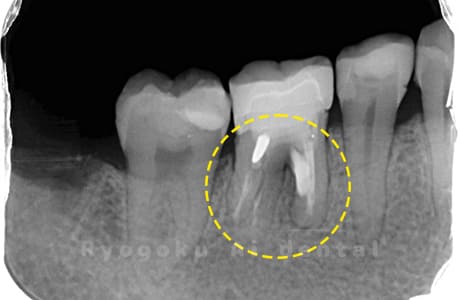

Case04

-

- 原因

- 右下6番パーフォレーション

- 治療内容

- パーフォレーションリペア

- 治療費用

- ¥66,000

右下奥歯が他院で行った治療後、腫れが引かないとのことでご来院された患者様です。近心根の遠心壁にパーフォレーションを認めたため、外科的にパーフォレーション部の修復を行いました。経過良好です。

<リスク・副作用>

手術後は痛み、腫れ、痺れ、青あざなどの副作用が生じます。痛みは痛み止めを処方しますが、腫れ、青あざは1週間程度生じる場合があります。また、部位によっては神経の走行が複雑で、痺れが残り、長期的にお薬を処方する場合があります。